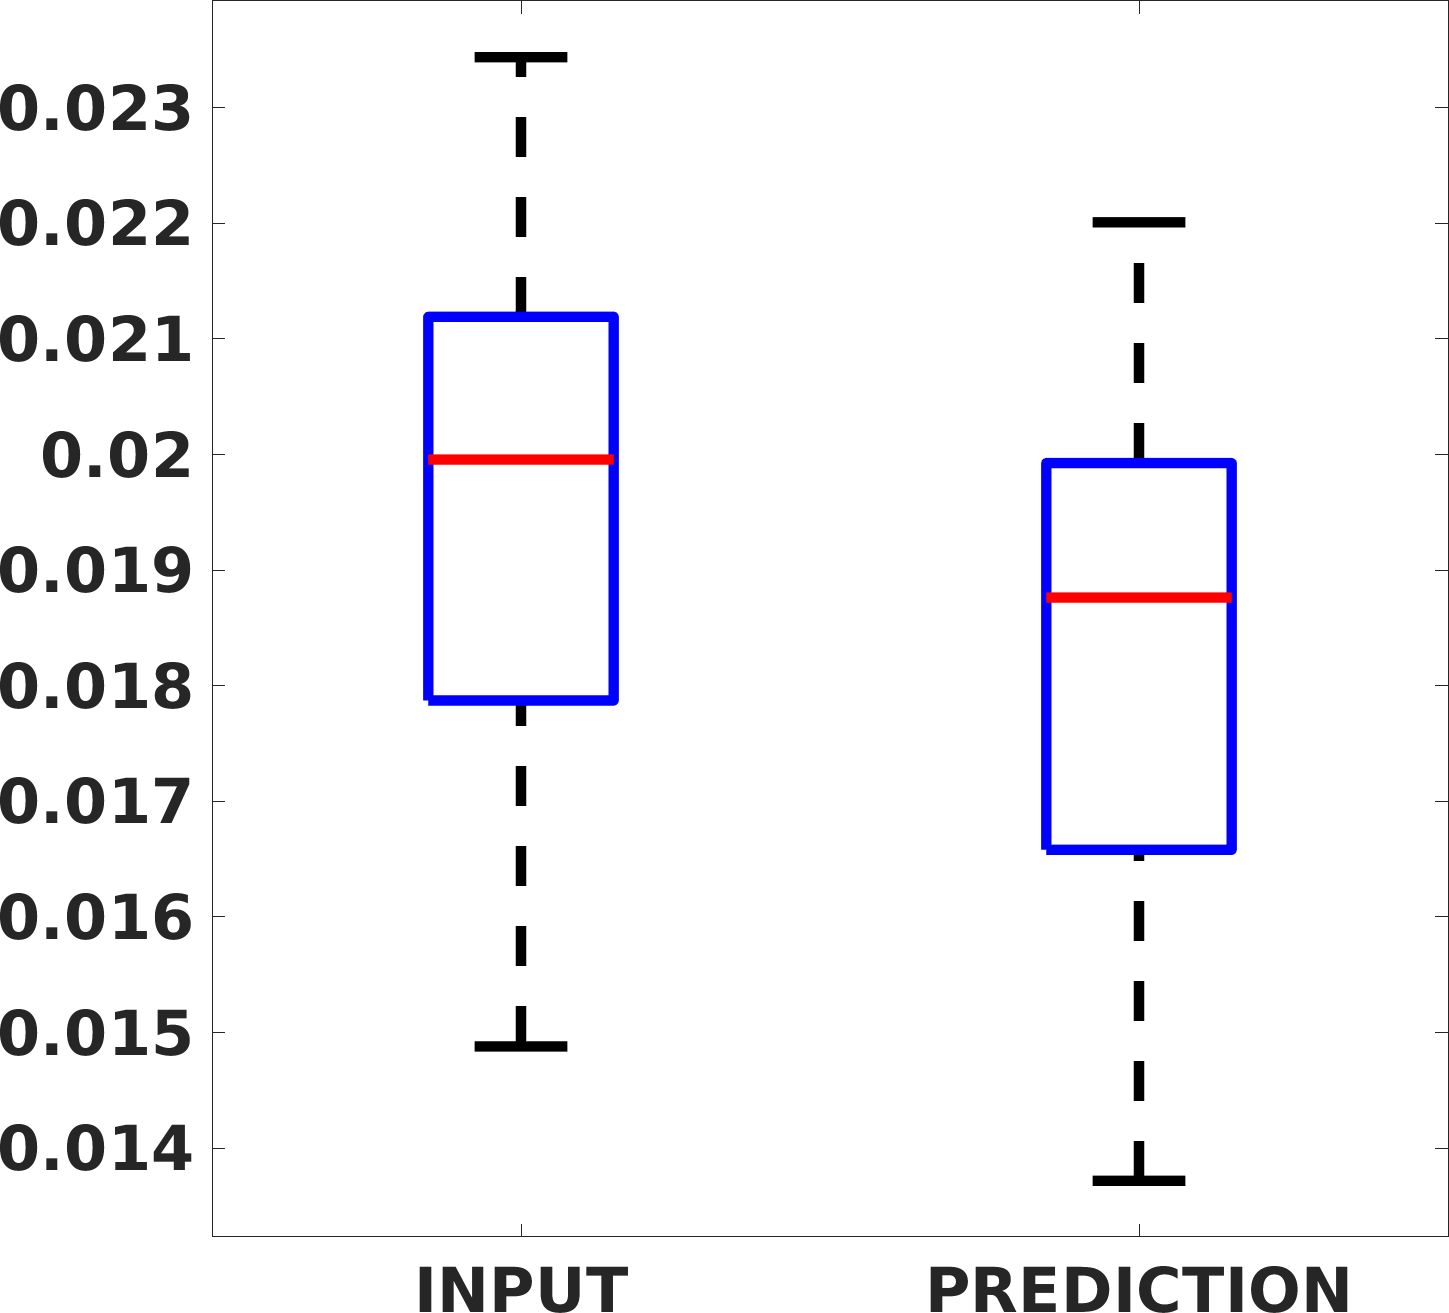

Fig. 7(a-b-c, left) shows the box plot of the statistics of the PSNR on three different anatomical districts, comparing the target images with the prediction and the cubic convolution, respectively. The metrics are computed on a data set of 200 images of the same district and with the same up-sampling factor. We report that the PSNR median value improves of on obstetric 2X raw images, on cardiac 2X raw images, and on abdominal raw 4X images.

Fig. 7(a-b-c, right) shows the histogram of the absolute value of the error with respect to the target image, of the prediction and Cubic convolution results, respectively. The histograms show the number of pixels where the prediction error is lower than 5 (i.e., the first bin of the histogram), which means very similar to the target when visually analysing the images. From the Cubic convolution to the predicted images, this value increases of on obstetric 4X raw images, on cardiac 4X raw images, and on abdominal 4X raw images.